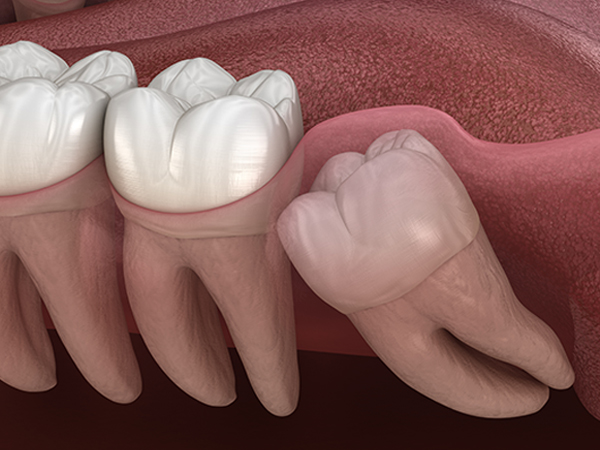

斜めに生えている親知らず

親知らずが斜めに生えていて、隣の歯にぶつかって圧迫してしまうタイプです。

このタイプが最も多く、虫歯になりやすいだけでなく、隣の歯を圧迫し、咬み合わせや歯並びに影響が出る場合もあるので、抜歯をおすすめします。

埋もれている水平埋伏の親知らず

歯ぐきの中で完全に真横に生えてしまうタイプです。この親知らずを水平埋伏智歯と言います。

このタイプは、ほとんどが下顎のケースです。真横に生えているので、抜歯の際は難易度が高く2~3つに砕いて分けて抜歯をします。

親知らずが横向きに生えていて、隣の歯を圧迫している埋伏歯の抜歯ケースです。このタイプは、抜歯が難しい分類になります。

当院では、このような難しい親知らずの抜歯ケースでもなるべく腫れずに、痛くなく抜歯することが可能です。